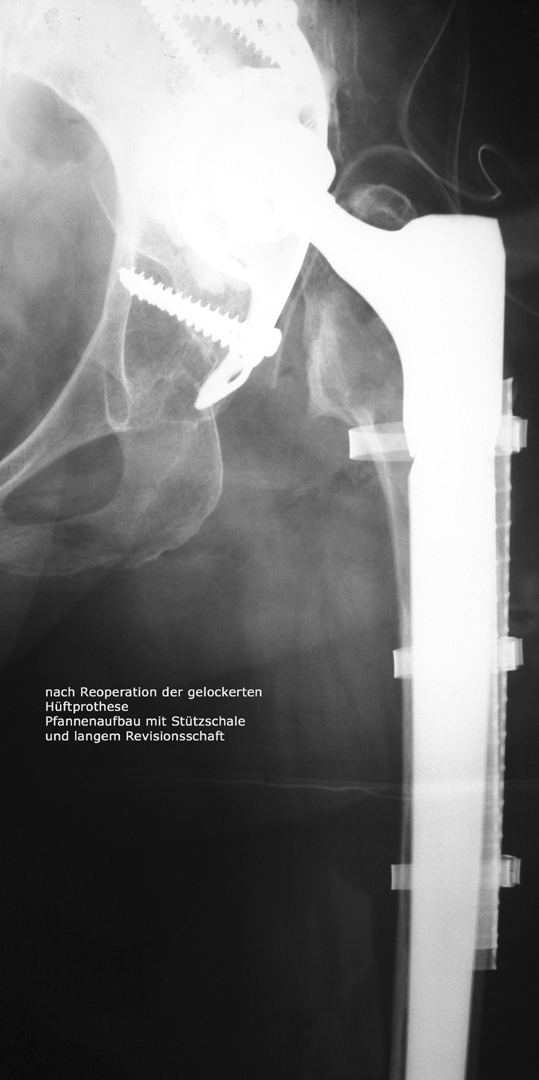

Reoperationen von gelockerten Gelenksprothesen

Reoperationen von gelockerten Gelenksprothesen sind anspruchsvolle operative Eingriffe , bei denen die Erfahrung des Operateurs und die Gabe zur richtigen Einschätzung der optimalen Versorgungsform von grosser Bedeutung ist. Reoperationen können dann erforderlich werden, wenn das Gefüge zwischen Knochen und Prothese aufgelockert wird – so kann eine Entzündung, ein vermehrter Abrieb der Prothesenteile, ein Bruch des die Prothese umgebenden Knochens aber auch Verletzungen der Weichteile eine Prothesenlockerung verursachen. Rasches Handeln ist dann angezeigt wenn der Patient über Schmerzen klagt, Röntgenuntersuchungen die Änderung der Prothesenposition

erkennen lassen oder Spezialuntersuchungen wie zum Beispiel eine Szintigraphie Hinweis auf eine Prothesenlockerung geben. Der operative Eingriff selbst ist für den Patienten belastend aber nur durch rasches Handeln kann die weitere Zerstörung von Knochen und Weichteilen verhindert werden.

Bild anklicken zum Vergrössern